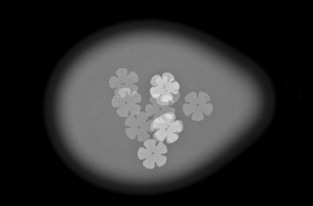

圧迫の必要性

厚みのある乳房の中にはたくさんの乳腺や脂肪などが重なって存在しています。

これらを均等に伸ばし組織同士の重なりを分離することで、小さなしこりや石灰化の粒をより見つけやすい画像にすることができます。

*実際に乳房を圧迫する時間は1枚の撮影で数十秒程度です。

画像1枚目:圧迫なし、画像2枚目:圧迫あり

水風船の中に花型のビーズをいれました。

厚みを約半分にしたことで、形がはっきり見えるようになります。